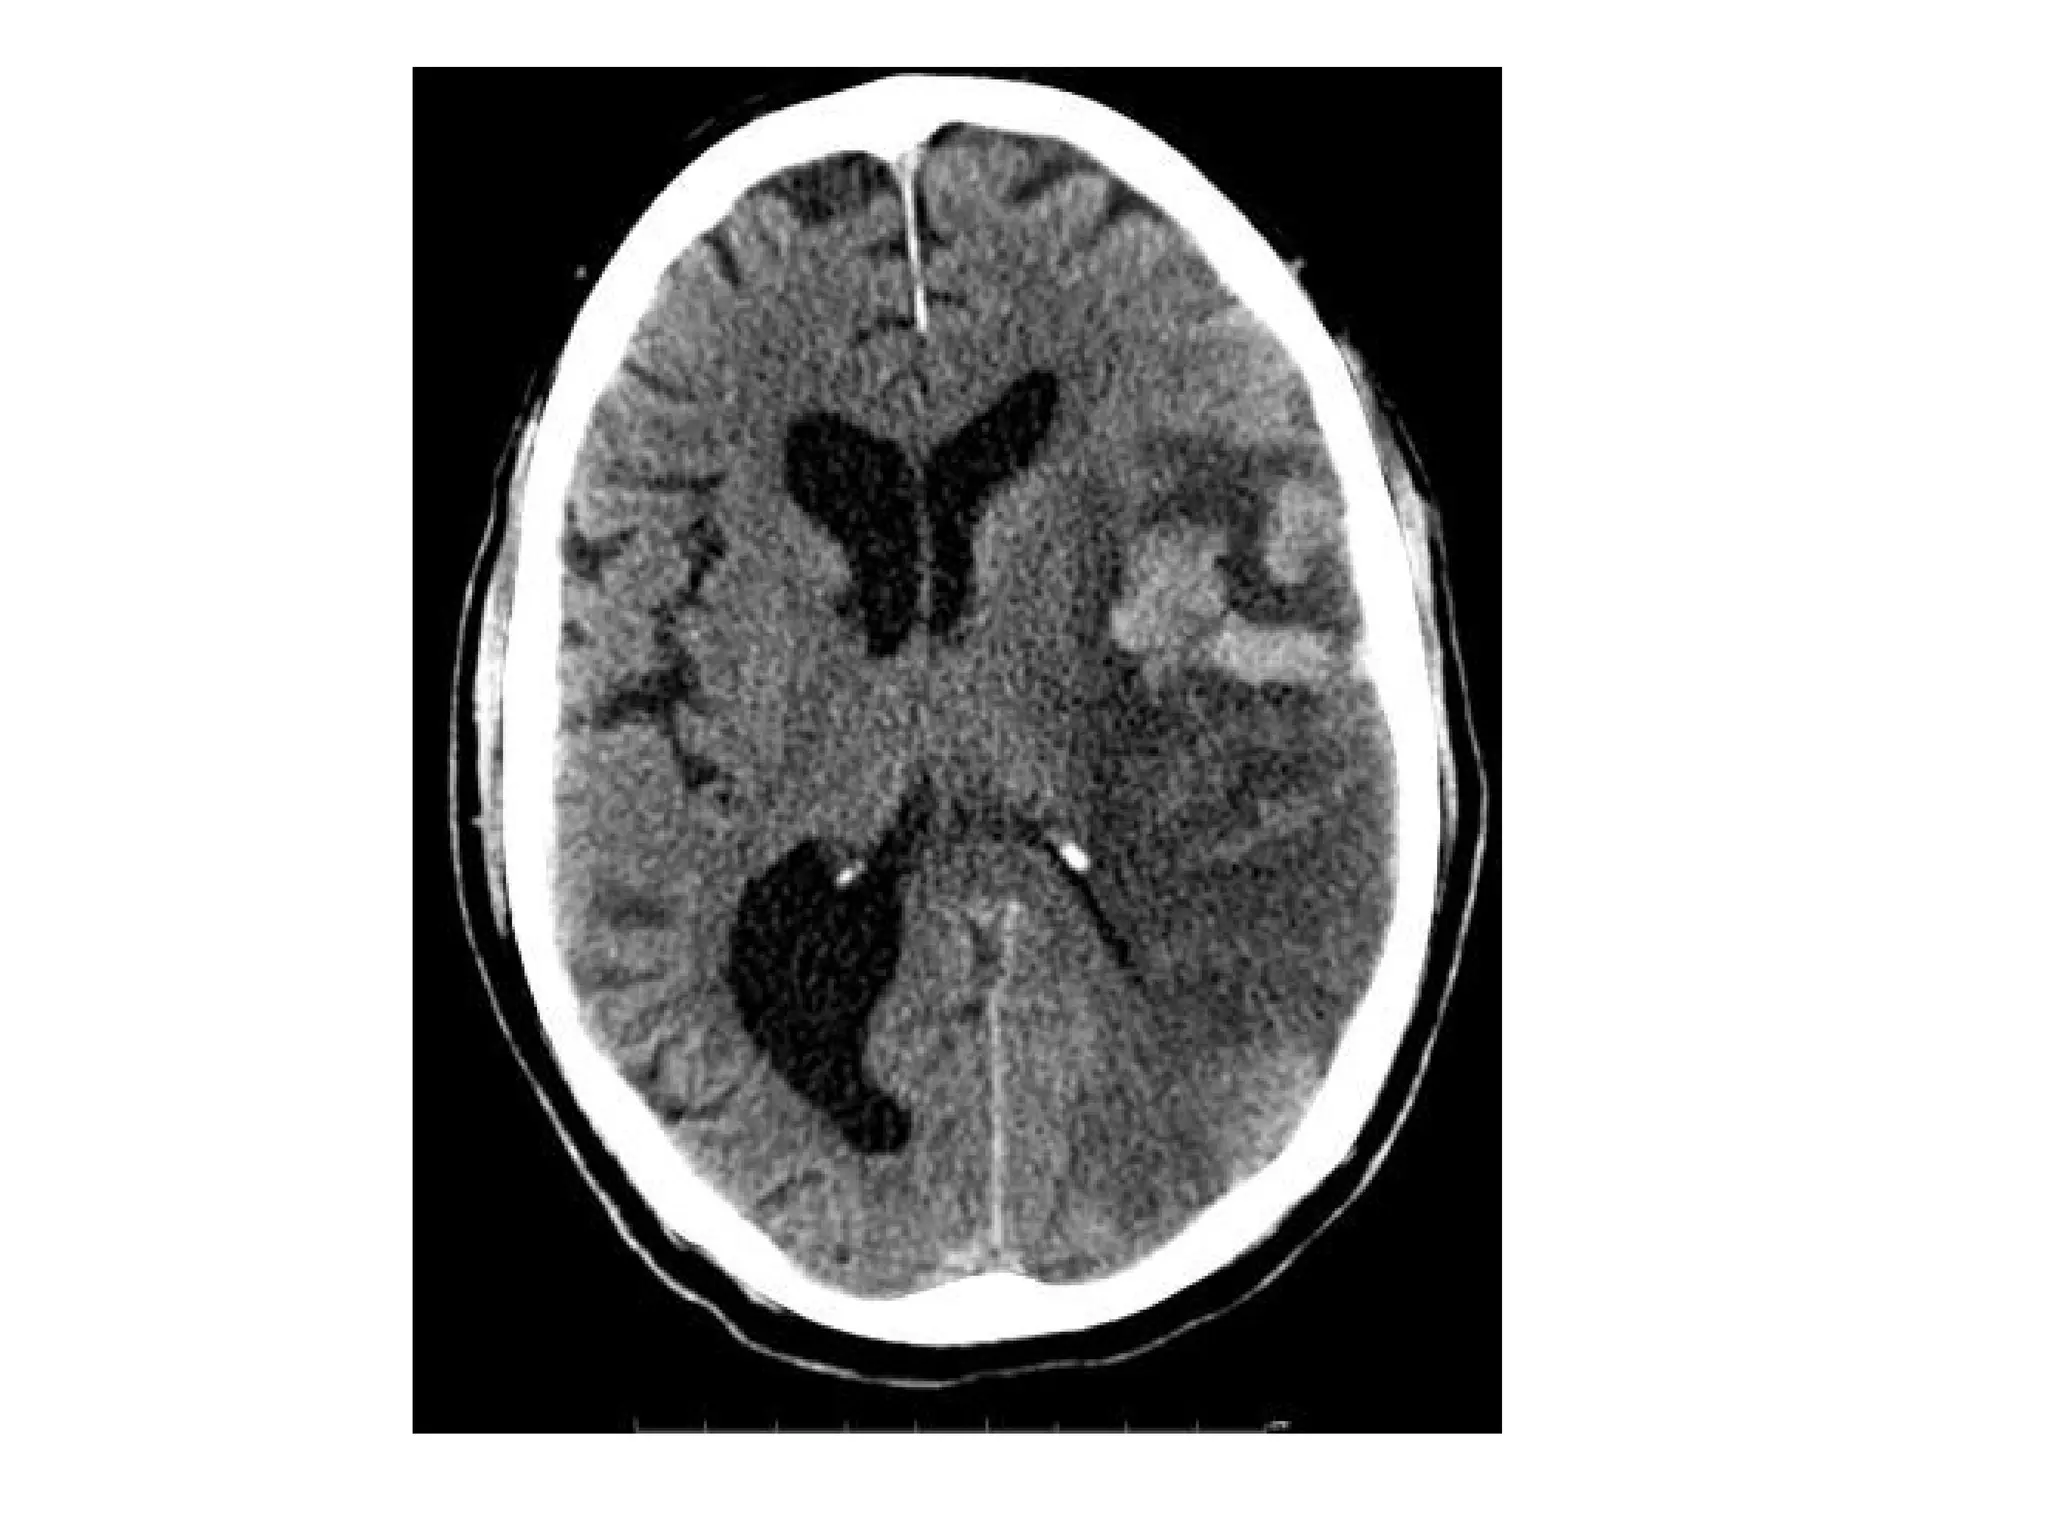

Patient with acute vision loss in the right half of the visual field ,

CT shows an infarction in the contralateral visual cortex , i.e

left occipital lobe

PCA infarction , notice the loss of gray / white matter differentiation in

the region of the left occipital lobe